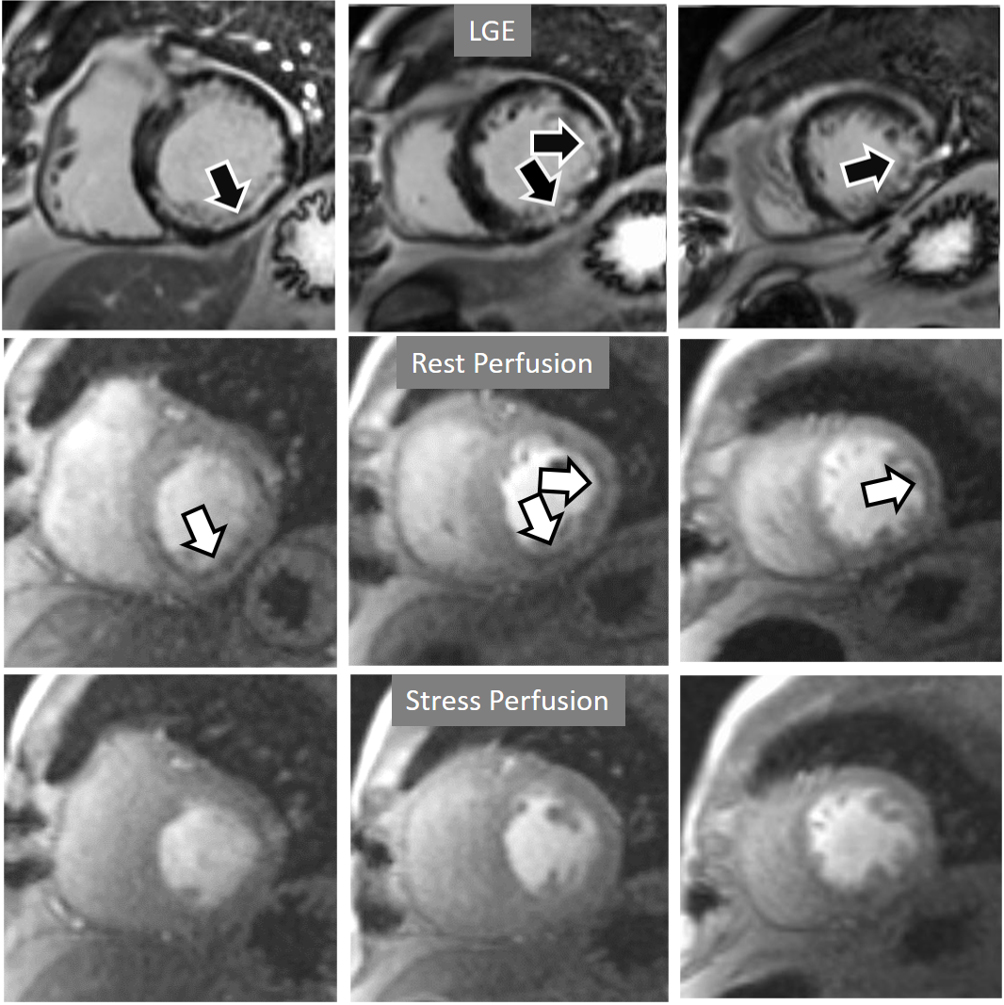

Perfusion defects in different territories can be detected in case of multivessel disease (Fig. 7) and, in patients with severe 3-vessel CAD, the perfusion study may show a global, intense, persistent defect which is readily recognizable (Fig. 8).

Fig. 7.Two-vessel perfusion defect. Stress perfusion defects at the anterior (white arrows) and inferior (black arrows) walls, not present at rest. Angiography (right panels) shows significant stenoses (white arrows) of the LAD (upper panel) and the right coronary artery (RCA) (lower panel).

Fig. 8.Three-vessel perfusion defect. Stress and rest studies in a patient with severe left main and 3-vessel CAD (arrows, on the right panels) showing an inducible perfusion defect in most, if not all, of the myocardial segments during vasodilatory stress.